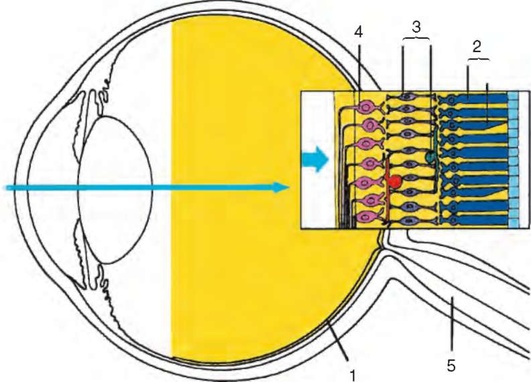

Рис. 1.5. Последовательность расположения нервных элементов в сетчатке: 1 - сетчатка; 2 - фоторецепторы; 3 - биполярные и другие нервные клетки, занимающие промежуточное положение; 4 - ганглиозные клетки; 5 - зрительный нерв